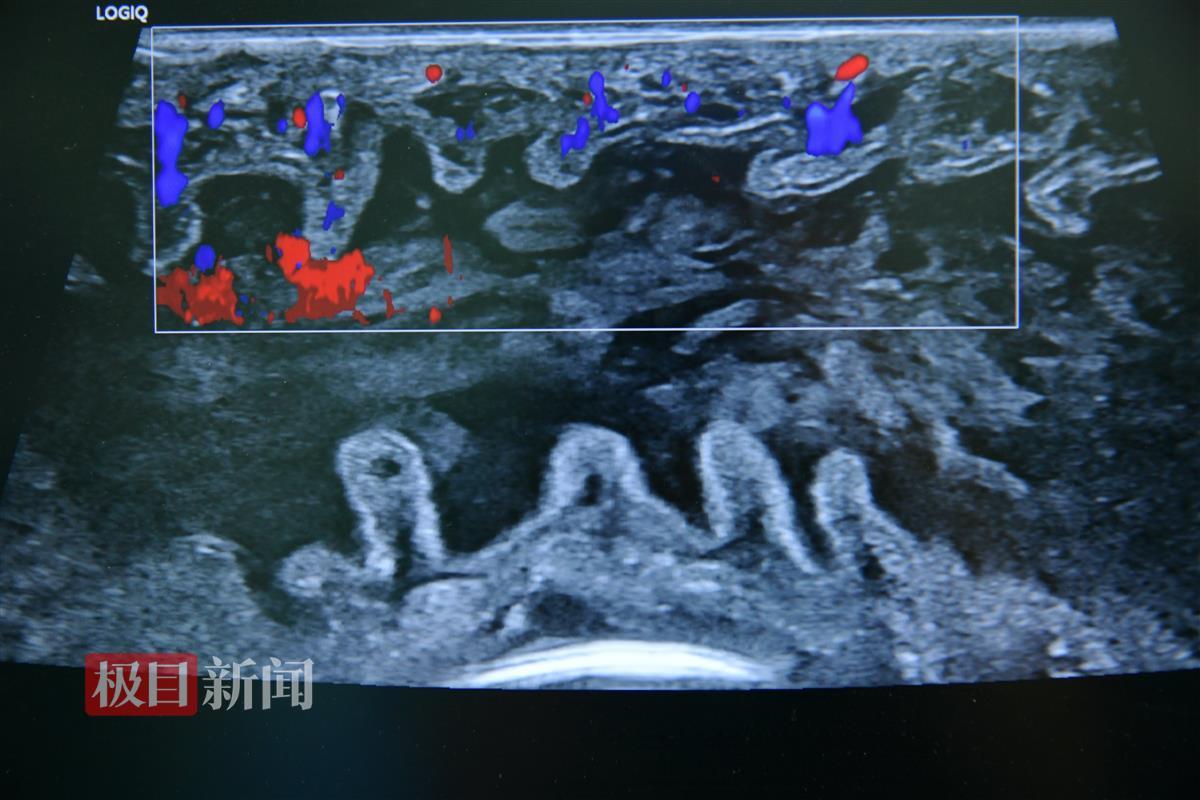

1月12日8时许,在该院车谷院区手术室团队、超声医学科的配合下,陶凯雄教授、吴轲教授团队取出小肠供体,在0至4℃的器官保护液中小心修剪,再精准植入到吕先生的体内。这个过程,专家要细致地重建血管、吻合小肠,每一步都容不得半点差错。

三个小时后,随着血供的恢复,移植的小肠肠壁逐渐恢复红润,并开始正常蠕动,这意味着手术成功完成。

移植的小肠供体恢复血流